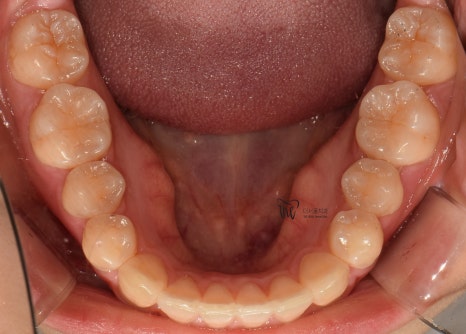

치열이 고르게 바뀐거 뿐만이 아니라

앞니들이 많이 앞쪽으로 뻐드러졌던

모습의 변화를 함께 볼 수 있으며

처음에 오셨을 때와는 다르게,

구강 내 어금니들이 위, 아래로 서로 다

고르게 다 맞물릴 수 있도록 바뀐 모습 또한

한번에 보실 수 있습니다.

+

턱관절 통증 까지도 말끔하게 사라졌으며,

예전과 다르게 식사를 할 때 조금 더

꼭꼭 씹어먹을 수 있는 느낌을 받아서

신세계..(?) 라는 표현을 쓰시네요.^^